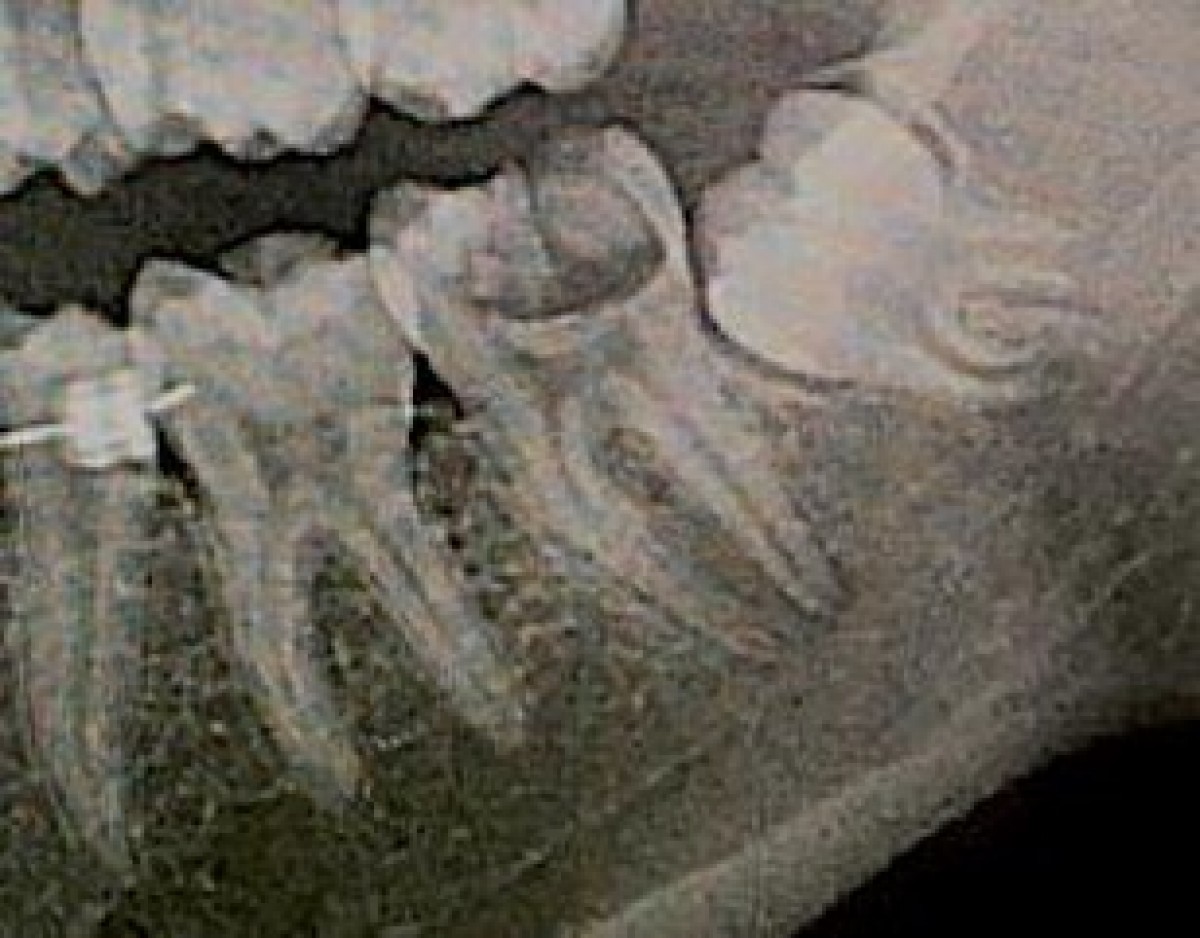

A 27-year-old woman underwent a visit in the Department of Endodontics at Tokyo Dental College Chiba Hospital for conservative treatment of the mandibular left second molar. Intraoral radiography and CBCT images showed a C-shaped root canal in the mesial root and resorption of the distal root due to impact of the crown of the horizontally impacted third molar. Extraction was therefore planned and the possibility of transplanting tooth 38 to replace 37 was considered. Multiple 3D models of these teeth were subsequently prepared based on computer-aided design (CAD) data obtained from CBCT images using a desktop 3D printer. The procedure was explained to the patient using the 3D models and surgical simulation. Finally the surgery was carried out. For temporary fixation to the adjacent tooth, adhesive resin was used.

Postoperative at 2 months showed no vitality of the transplanted tooth, so an endodonthic treatmet was performed. At one year of follow up, any anomaly was found and the patient was able to chew with the transplanted tooth and radiographs indicated a successful postoperative clinical course.